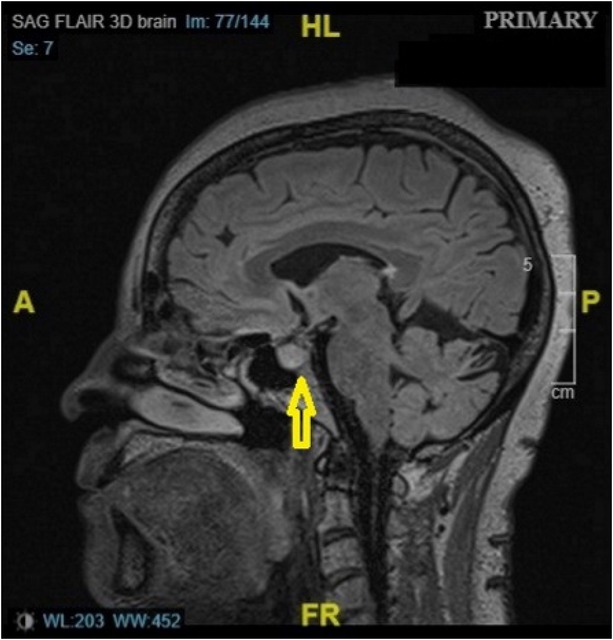

MRI scan of the patient showing pituitary enhancement (yellow arrow). MRI: magnetic resonance imaging. A: anterior; P: posterior; HL: head length; FR: frequency.

A 66-year-old woman with metastatic melanoma of the right chest presented with a month history of intermittent abdominal pain, diarrhea, nausea, and fatigue, which worsened in the last week. Patient did not endorse any fever, vomiting, cough, or dysuria. Her last immunotherapy regimen with ipilimumab and nivolumab started two months ago. On presentation, she was hypotensive with a blood pressure 85/53 mmHg and heart rate 56/min. She was afebrile and was maintaining normal oxygen saturation in room air. During hospitalization, a new-onset headache in the forehead with blurry vision had developed in the patient. Laboratory investigations demonstrated a serum sodium 124 mmol/L (low), potassium 4 mmol/L, and a negative Clostridium difficile stool assay. Further tests revealed a serum osmolality of 259 mOsm/ kg (low), urine osmolality of 195 mOsm/ kg, urine sodium of 59 mmol/L (high), and a thyroid-stimulating hormone (TSH) level of 0.404 μIU/mL (low). Final investigations included a morning serum cortisol of 0.1 μg/dL (low), adrenocorticotropic hormone (ACTH) level of 3.4 pg/mL (low), T3 of 2.01 pg/mL (low), free T4 of 0.50 ng/ dL (low), luteinizing hormone (LH) of 1.1 mIU/mL (low), follicular stimulating hormone (FSH) of 6.8 mIU/mL (low), and a prolactin level of 1.3 ng/mL (low). A magnetic resonance imaging (MRI) of the brain demonstrated an enlarged pituitary gland suggesting hypophysitis (Figure 1). The patient was immediately treated with methylprednisolone at 2 mg/ kg/day, and endocrinology was consulted. Hyponatremia and neurologic symptoms improved drastically with treatment. Methylprednisolone was transitioned to hydrocortisone, and levothyroxine was added to the regimen. Upon discharge, the patient was given emergency hydrocortisone pens and follow-up appointment with the endocrinologist.

The patient was consistently hypotensive and bradycardic despite adequate fluid resuscitation. Hyponatremia was key evidence that led to the diagnosis of secondary adrenal insufficiency, after ruling out other causes. Further investigations in that direction revealed decreased levels of cortisol, ACTH, FSH, LH, TSH, and prolactin, confirming the diagnosis of hypophysitis. In acute stage of hypophysitis, pituitary enhancement and swelling can be observed on MRI, and the same was demonstrated in our patient.[3]